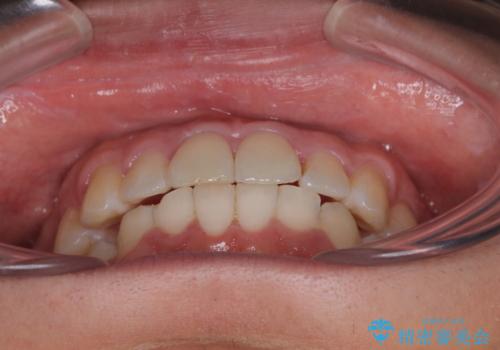

前方に捻れた前歯を治したい インビザライン矯正治療

- 前歯のデコボコを治したいとのことで来院された患者様です。

上下顎ともに歯列全体の後方移動とIPR(歯と歯の間を削る)によってデコボコが解消するように設計し、インビザラインにより治療を行うこととしました。